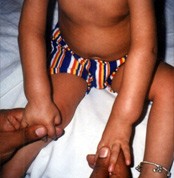

cdh1

cdh2

cdh4